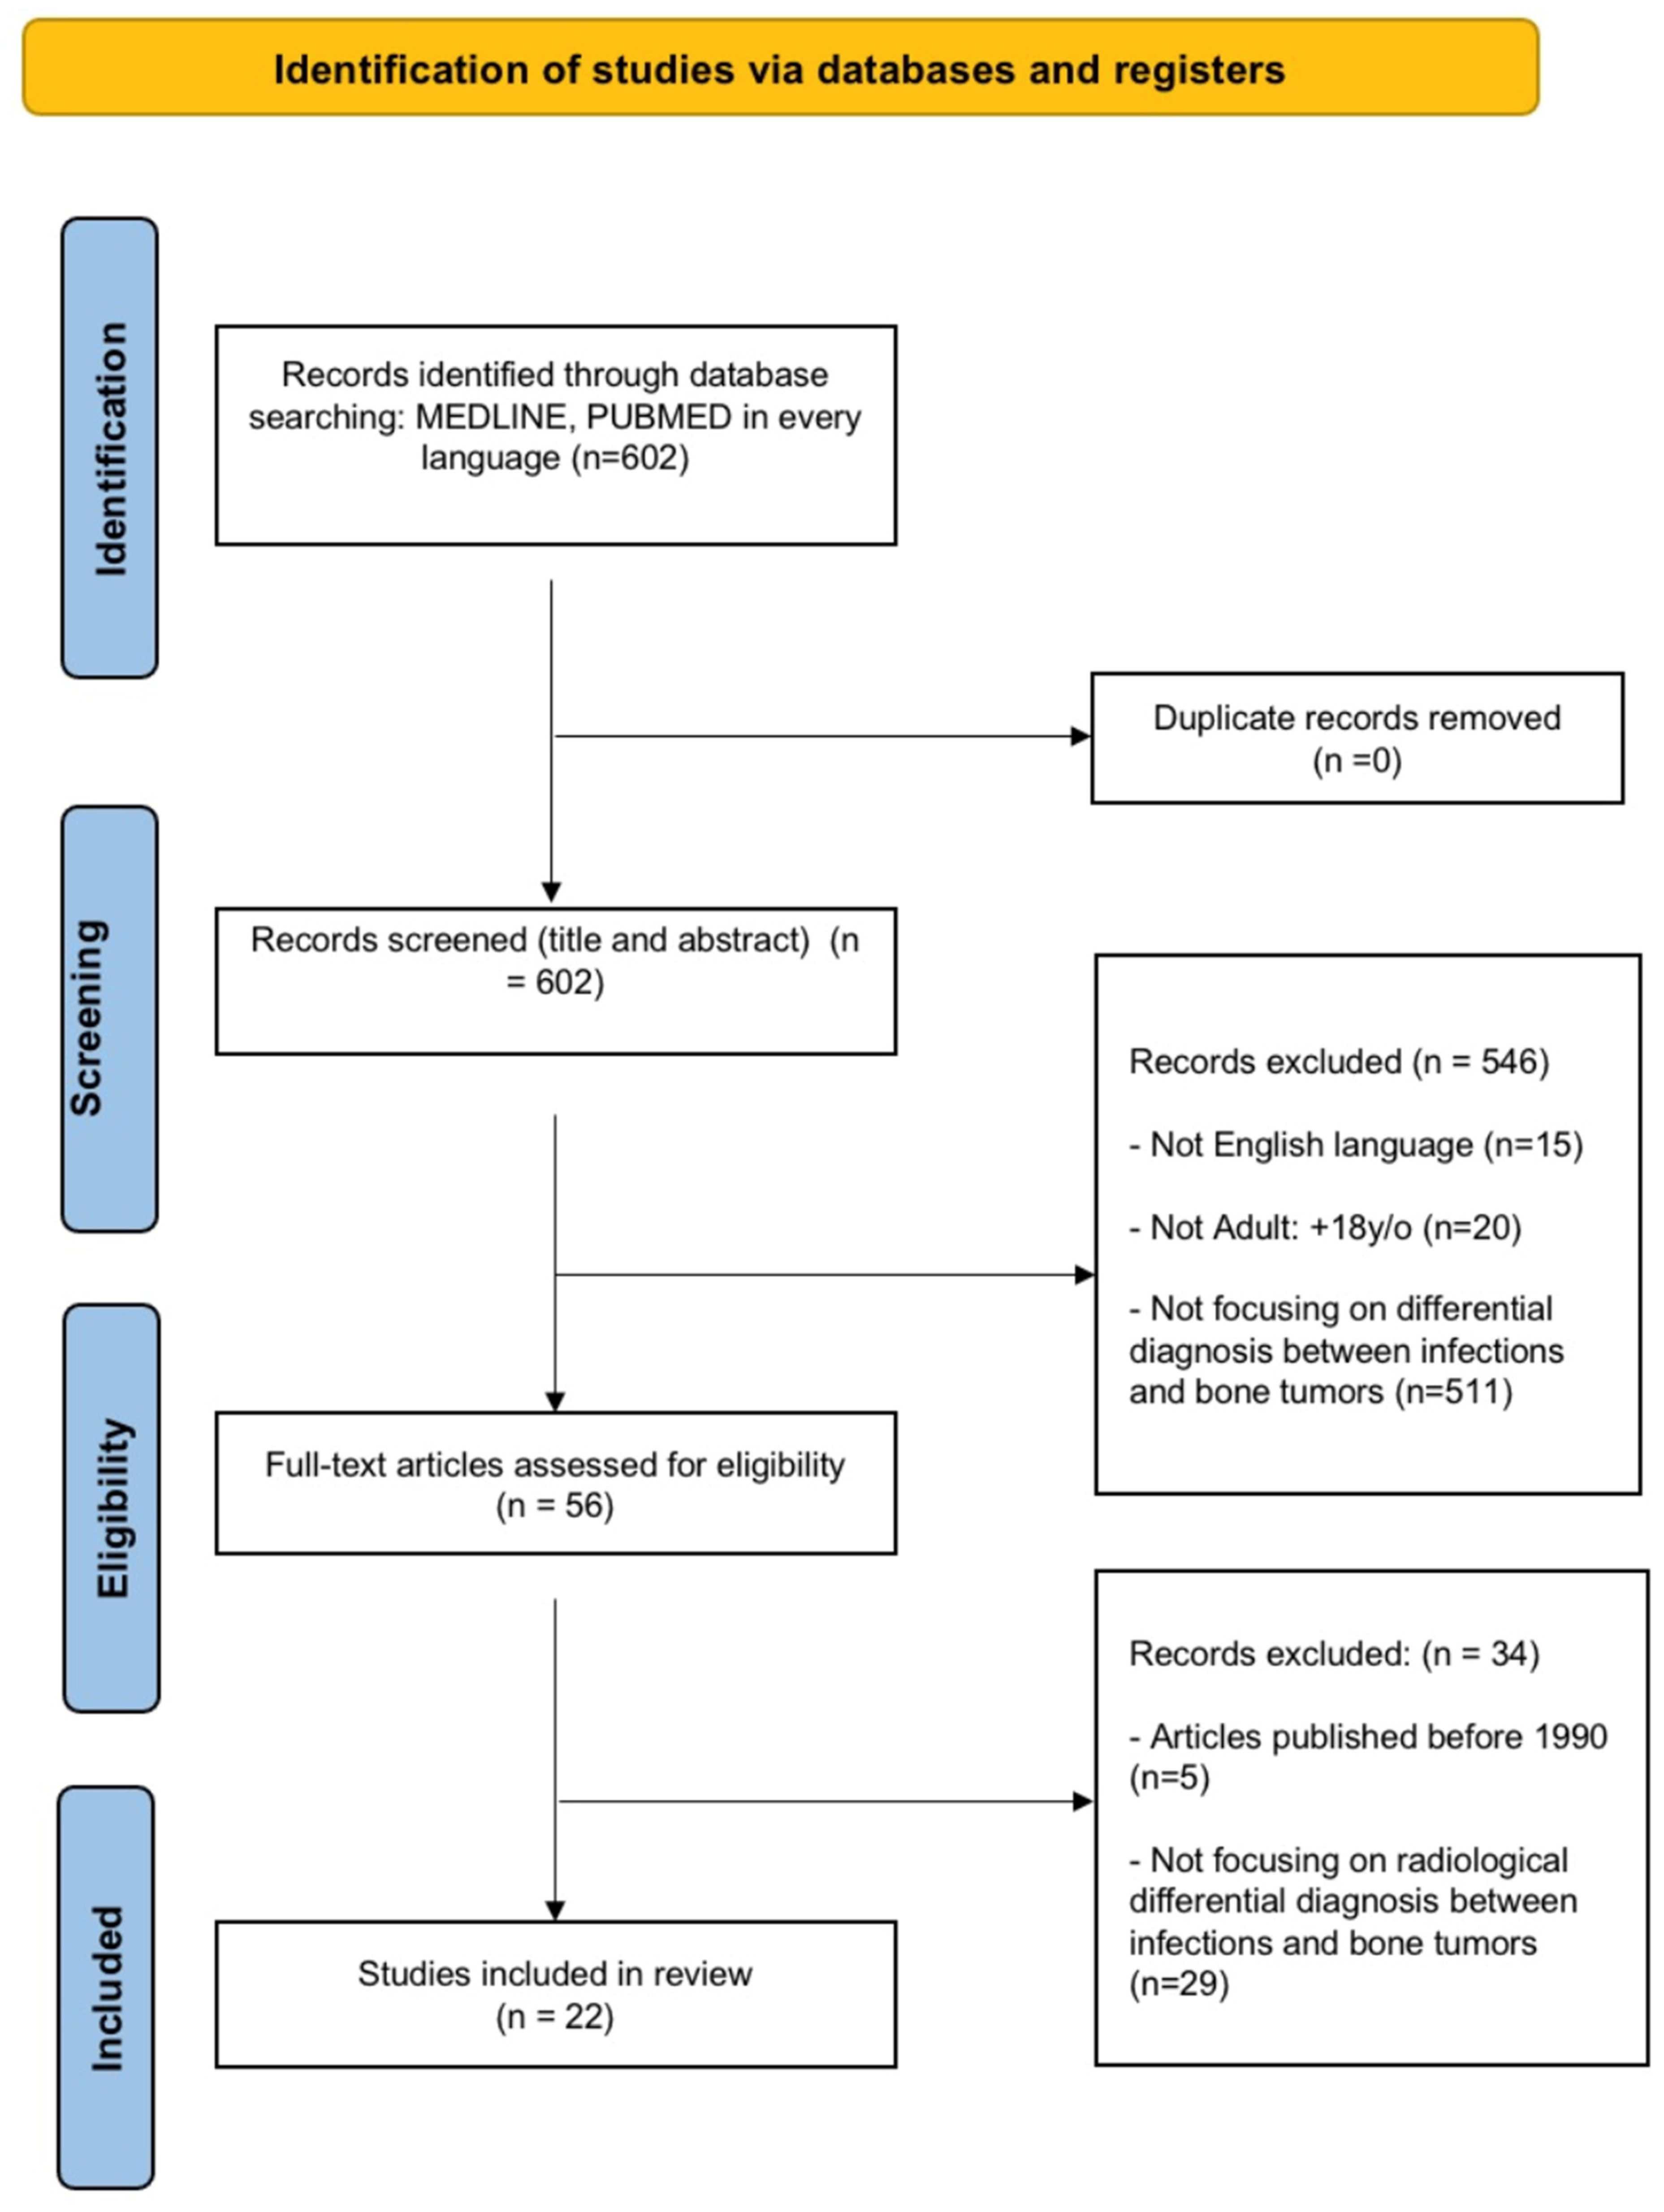

2. Material and Methods

2.1. Study Design

2.2. Information Sources and Search Strategy

2.3. Inclusion Criteria

- -

- Papers in English;

- -

- Papers including patients older than 18;

- -

- Papers providing qualitative results on radiological differential diagnosis between spinal tumors and spinal infections, focusing on findings that are useful in CT scan and MRI;

- -

- Retrospective or prospective studies including randomized controlled trials, non-randomized trials, cohort studies, case–control studies, case series and other reviews of the literature.

2.4. Exclusion Criteria

- Articles that did not provide clear results on radiological differential diagnosis between spinal tumors and spinal infections;

- Articles with patients 18 or younger.

3. Results

3.1. Characteristics of Included Studies